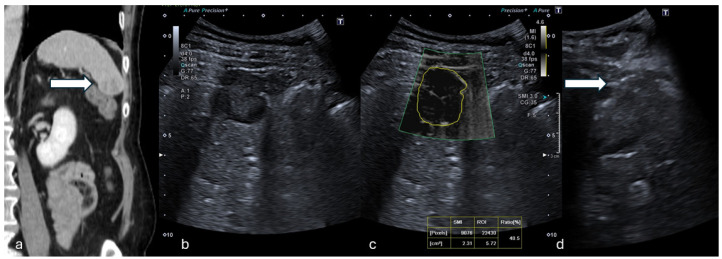

Objectives: This study aims to assess the potential role of the ultrasound (US) monochromatic Superb Microvascular Index (mSMI) to predict malignancy of solid focal lesions, correlating the vascular index (VI) with bioptic histological results.

Methods: In this single-center retrospective analysis, patients undergoing percutaneous US-guided biopsy of solid lesions were considered. Biopsy indication was given by a multidisciplinary team evaluation based on clinical radiological data. Exclusion criteria were: unfeasible SMI evaluations due to poor respiratory compliance, locations not appreciable with the SMI, previous antiangiogenetic chemo/immunotherapies, and inconclusive histological reports. The mSMI examination was conducted in order to visualize extremely low-velocity flows with a high resolution and high frame rate; the VI was semi-automatically calculated. All bioptic procedures were performed under sole US guidance using 16G or 18G needles, immediately after mSMI assessment.

Results: Forty-four patients were included (mean age: 64 years; 27 males, 17 females). Liver (15/43), kidneys (9/43), and lymph nodes (6/43) were the most frequent targets. At histopathological analysis, 7 lesions were benign and 37 malignant, metastasis being the most represented. The VI calculated in malignant lesions was statistically higher compared to benign lesions (35.45% and 11% in malignant and benign, respectively; p-value 0.013). A threshold VI value of 15.4% was identified to differentiate malignant lesions. The overall diagnostic accuracy of the VI with the mSMI was 0.878, demonstrating a high level of diagnostic accuracy.

Conclusions: In this study, the mSMI analysis of solid focal lesions undergoing percutaneous biopsy significantly correlated with histological findings in terms of malignant/benign predictive value, reflecting histological vascular changes in malignant lesions.